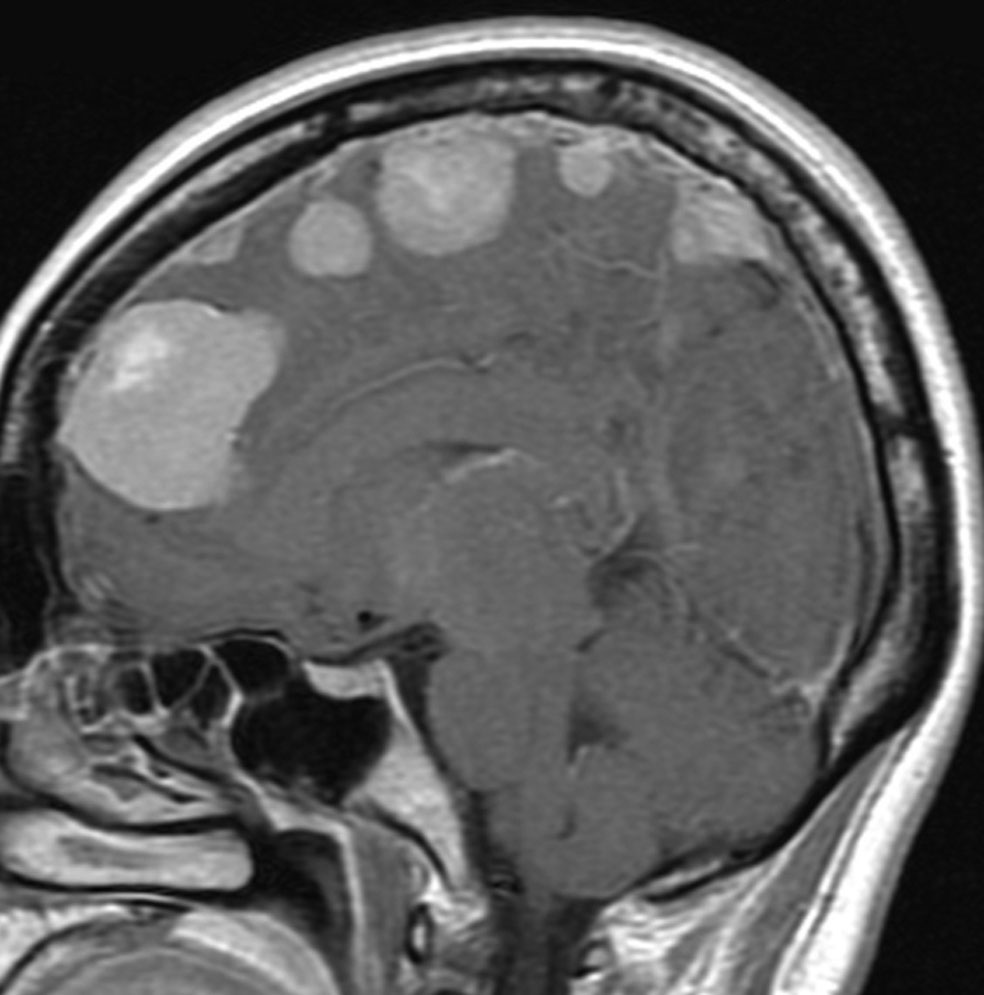

全髄膜の腫瘍化,NF-2

テント下を含めて頭蓋内の全ての髄膜が同時に腫瘍化してきます。この患者さんはNF-2なのですが,NF-2がない患者さんにもmeningiomatosisはあります。脳圧亢進による視神経乳頭萎縮で両側の視力が無くなるというような症状が出ます。これは手術適応がないタイプです。